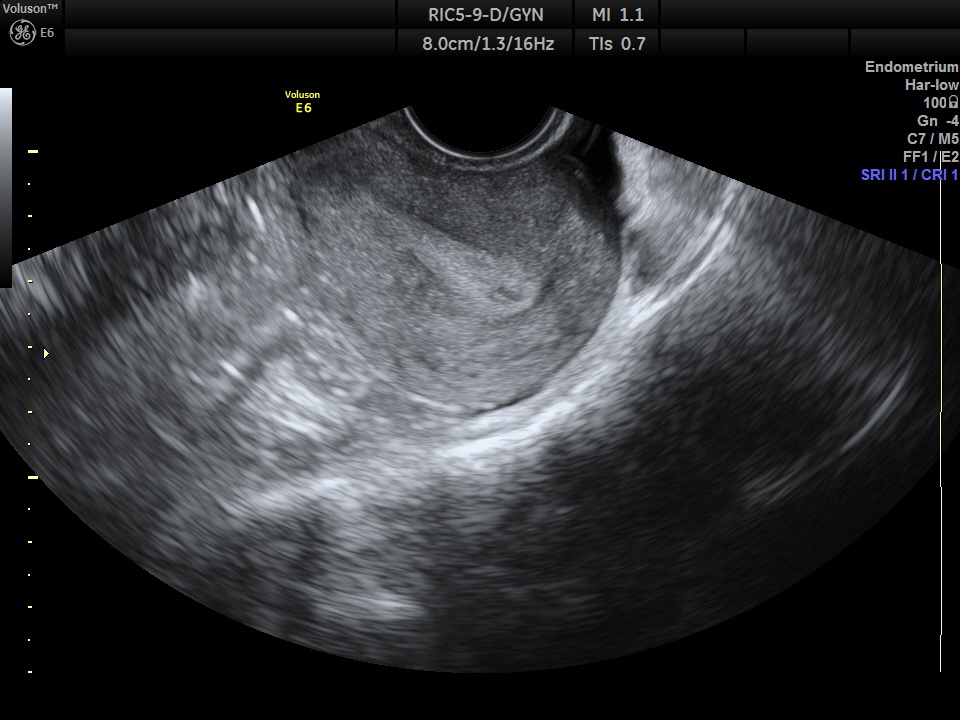

Почему нельзя делать УЗИ матки

Ультразвуковое исследование (УЗИ) - один из самых популярных и безопасных методов диагностики в гинекологии. Однако в последнее время растёт тревожная тенденция: женщины делают УЗИ матки «на всякий случай» или по собственному желанию, без медицинских показаний. Врачи предупреждают - это не всегда необходимо и может даже навредить. Давайте разберёмся почему.

УЗИ - это безопасно. В чём тогда проблема?

Да, ультразвук сам по себе не наносит вреда организму. Но есть нюансы:

1. Риск гипердиагностики. Часто при обследовании находят функциональные кисты, мелкие узлы, которые являются вариантом нормы. В результате женщине ставится диагноз, начинается ненужное лечение, стрессы и бесконечные повторные обследования.

2. Неинформативное исследование в «неправильные» дни цикла. Например, делать УЗИ на 10-й день цикла бессмысленно для диагностики эндометриоза или гиперплазии — эндометрий ещё не достиг нужной толщины. В результате - ложноотрицательные или ложноположительные выводы.

3. УЗИ - это не профилактика. Это метод диагностики, а не средство профилактики. Если нет симптомов (боли, кровотечений, нарушений цикла), вы регулярно (раз в год) сдаете мазок на онкоцитологию - постоянные УЗИ без назначения врача не несут смысла. Остановитесь на УЗИ 1 раз в год, если нет других рекомендаций врача.

Когда УЗИ действительно необходимо?

УЗИ - важный инструмент в руках врача. Но это не тот метод, который нужно применять регулярно без показаний. Главное - прислушиваться к своему телу и консультироваться с грамотным специалистом, который назначит УЗИ тогда, когда оно действительно нужно, а не «на всякий случай».